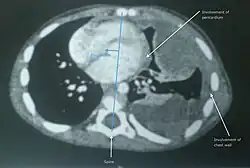

A soft-tissue sarcoma (STS) is a malignant tumor, a type of cancer, that develops in soft tissue.[1] A soft-tissue sarcoma is often a painless mass that grows slowly over months or years. They may be superficial or deep-seated. Any such unexplained mass must be diagnosed by biopsy.[2] Treatment may include surgery, radiotherapy, chemotherapy, and targeted drug therapy.[3] Bone sarcomas are the other class of sarcomas.

Soft-tissue sarcomas commonly originate in the upper body, in the shoulder or upper chest. Some symptoms are uneven posture, pain in the trapezius muscle, and cervical inflexibility [difficulty in turning the head].[12] The most common site to which soft-tissue sarcoma spreads is the lungs.[13]